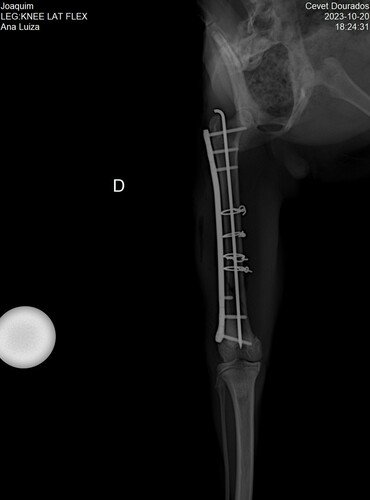

Em Nova Andradina, no dia 20/10, Joaquim foi consultado às pressas pelo veterinário, que disse que o caso era provavelmente cirúrgico. Depois do raio-x, do qual Joaquim precisou ser sedado de tanta dor, veio a notícia: ele precisaria ser operado às pressas numa cirurgia de Osteossintese do Femur Direito, pois estava fraturado em 3 partes.

A cirurgia custava R$ 3.795, além de R$ 435 da consulta + raio-x.